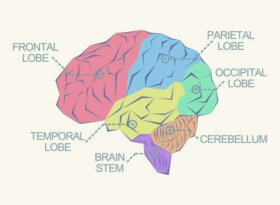

뇌의 여러 가지 엽은 각자가 수행하는 기능에 따라 나뉘는 뇌의 피질이다. 다시 말해, 뇌의 엽은 기능적이고 해부학적인 부분이라고 할 수 있다. 또 이러한 구분은 인간으로서 각 기능의 기원을 식별하는 데에도 도움이 된다. 더 읽어보기: 우울증이 뇌에 끼치는 물리적 영향 4가지 실제로…